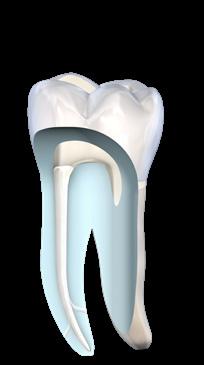

Every endo is unique. And so is FQ: innovative system to make the treatment easier, more efficient and safer. It is an impressive all-in-one-solution that transfers Komet’s experience into a new generation of files. This new rotary nickel-titanium file system allows for an effective and minimally invasive treatment of difficult root-canals. The innovative variably tapered file core has a double-S cross section and offers maximal flexibility and an excellent cutting performance. The prebendable files cut easily and grant a pleasant and safe working experience.

Double-S cross section.

Efficient treatment thanks to the excellent cutting performance. The narrow core of the file allows for optimal flexibility.

Variably tapered file core*

The variably tapered file core enlarges the chip space. Infected tissue is transported out of the canal more efficiently and the duration of the treatment is shortened.

Thanks to the heat-treated material, the variably tapered file core is very flexible. The file follows the anatomy even in very curved canals, making the treatment safer.

Unique - Double-S cross-section and a variably tapered file core*

Infected tissue is evacuated from the canal even more efficiently, thus optimizing the treatment time.

Large chip space for optimum removal of debris

Adapted instrument core for high flexibility